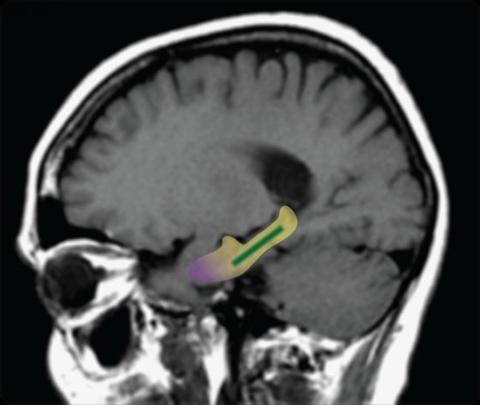

남극 기지에서 체류 전, 후에 팀원들의 뇌를 자기공명영상(MRI)으로 관찰한 결과, 뇌 해마의 내부에 있는 ‘치아 이랑’, 또는 ‘치상회’라고 부르는 기관이 작아진 것을 발견했다. 이 부위는 사람이나 포유류의 공간적 사고와 선택적 주의력에 영향을 미치며, 중요하지 않은 정보를 필터링하는 데 필요하다.

독일의 노이마이어 III(Neumayer III) 남극 연구기지에서 14개월 동안 격리되어 체류한 8명의 연구원을 조사한 결과, 공간적 사고와 기억 통합을 담당하는 뇌 해마의 ‘치상회(dentate gyrus)’ 용량이 평균 7% 감소한 것으로 나타났다. 이 연구는 지난 5일 ‘뉴잉글랜드 의학저널(New England Journal of Medicine)’에 발표됐다.